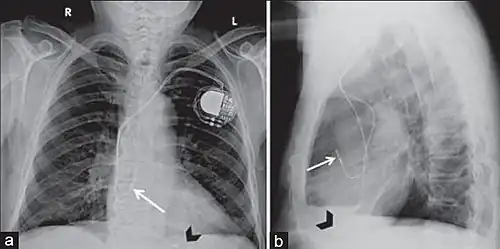

Permanent transvenous pacing

Permanent pacing with an implantable pacemaker involves transvenous placement of one or more pacing electrodes within a chamber, or chambers, of the heart, while the pacemaker is implanted under the skin below the clavicle. The procedure is performed by incision of a suitable vein into which the electrode lead is inserted and passed along the vein, through the valve of the heart, until positioned in the chamber. The procedure is facilitated by fluoroscopy which enables the physician to view the passage of the electrode lead. After satisfactory lodgement of the electrode is confirmed, the opposite end of the electrode lead is connected to the pacemaker generator.

A pacemaker may be implanted whilst a person is awake using local anesthetic to numb the skin with or without sedation, or asleep using a general anesthetic.[25] An antibiotic is usually given to reduce the risk of infection.[25] Pacemakers are generally implanted in the front of the chest in the region of the left or right shoulder. The skin is prepared by clipping or shaving any hair over the implant site before cleaning the skin with a disinfectant such as chlorhexidine. An incision is made below the collar bone and a space or pocket is created under the skin to house the pacemaker generator. This pocket is usually created just above the pectoralis major muscle (prepectoral), but in some cases the device may be inserted beneath the muscle (submuscular).[26] The lead or leads are fed into the heart through a large vein guided by X-ray imaging (fluoroscopy). The tips of the leads may be positioned within the right ventricle, the right atrium, or the coronary sinus, depending on the type of pacemaker required.[25] Surgery is typically completed within 30 to 90 minutes. Following implantation, the surgical wound should be kept clean and dry until it has healed. Some movements of the shoulder within a few weeks of insertion carry a risk of dislodging the pacemaker leads.[25]